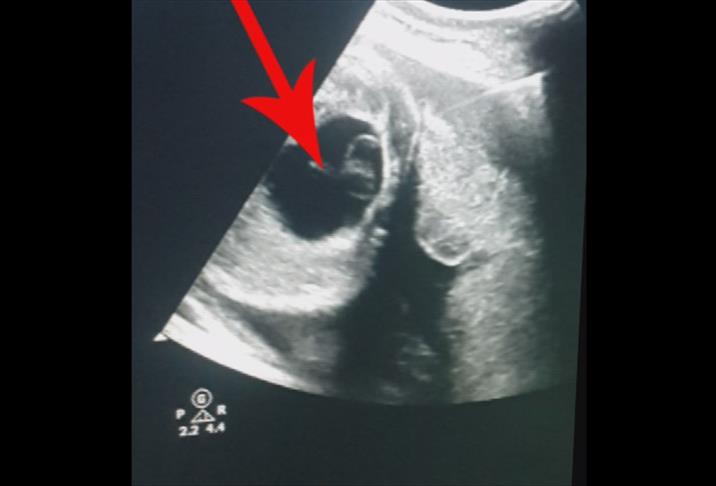

Yumurtalık kisti, yumurtalık içinde veya yüzeyinde sıvı dolu kesecikler şeklinde oluşan yapılar olarak tanımlanır. Çoğu kist iyi huylu olup kendiliğinden kaybolabilir. Ancak bazı kistler büyüyebilir, ağrıya veya adet düzensizliklerine yol açabilir. Yumurtalık kesilmesi, tıbbi adıyla ooforektomi, bir veya her iki yumurtalığın cerrahi yöntemle alınmasıdır. Genellikle büyük kistler, kanser riski taşıyan kistler veya sürekli ağrıya neden olan durumlarda uygulanır. Ameliyat laparaskopik veya açık cerrahi tekniklerle yapılabilir.